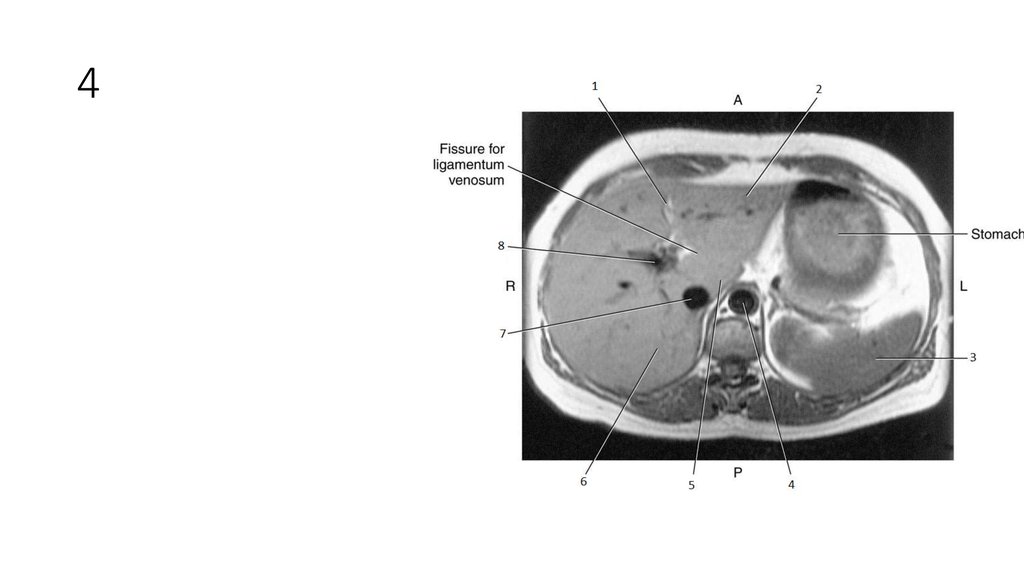

16. 1

• Falciform Ligament

18. 2

• Left lobe of Liver

21. 3

22. 4

• Aorta

25. 5

• Caudate Lobe of Liver

26. 6

• Right Lobe of Liver

29. 7

• Inferior Vena Cava (IVC)

30. 8

• Portal Vein